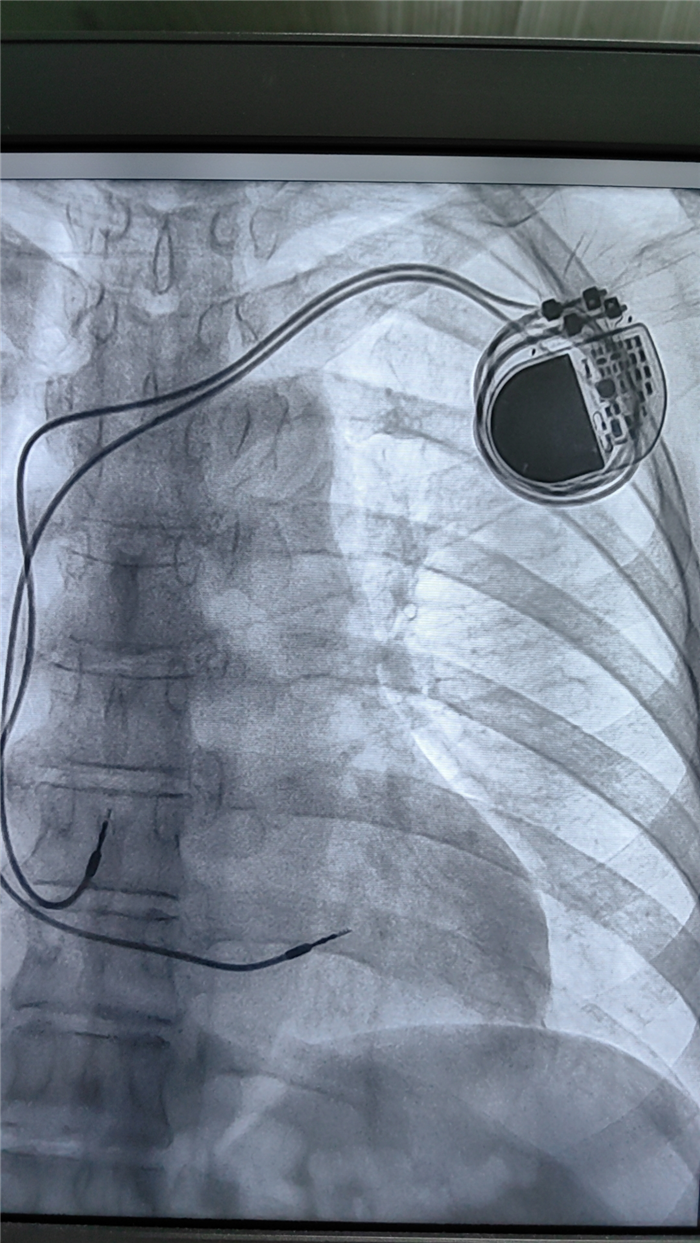

起搏器植入成功

近日, 西藏阜康醫(yī)院 心內(nèi)科在朱永彪主任的帶領(lǐng)下,成功開(kāi)展了永久心臟起搏器植入術(shù),整個(gè)植入過(guò)程順利,心理疏導(dǎo)到位,患者接受程度良好,達(dá)到了預(yù)期效果。

患者植入后無(wú)并發(fā)癥及任何不適,該項(xiàng)目的開(kāi)展標(biāo)志我院在不斷提高心血管介入技術(shù)、保障患者生命安全方面邁進(jìn)了一大步。

這一臨床技術(shù)的熟練開(kāi)展,對(duì)心動(dòng)過(guò)緩、傳導(dǎo)阻滯患者以及需要提高心率、度過(guò)疾病危險(xiǎn)期的患者提供了技術(shù)支撐與安全保障,將為更多的心臟病患者消除病痛。